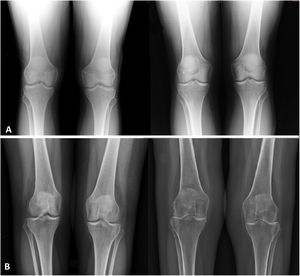

We were able to observe the radiological evolution of 12 patients who presented radiographies before and after radiosynoviorthesis. Of these, 9 presented radiological stability with a median follow-up of 43 months (mean 36.4; range 7–84), 2 progressed from KL grade 3 to grade 4 within 24 and 18 months, respectively, and 1 progressed from KL grade 1 to grade 4 in 24 months, although, as shown, there was great variability in patient follow-up due to the lack of standardization in the times to perform the intervention. The different distribution in the radiological evolution of the 12 patients is shown in Fig. 4, and the radiographic findings of 2 specific patients are shown in Fig. 5.

A. Patient with radiological stability with Kellgren-Lawrence grade 1 at two years of evolution. The image of the left was obtained prior to radiosynovectomy while the image on the right is from after the intervention. B. Patient with radiological progression with Kellgren-Lawrence grade 1 (image on the left is prior to radiosynovectomy) to 4 (image of the right after radiosynovectomy) at two years of evolution.